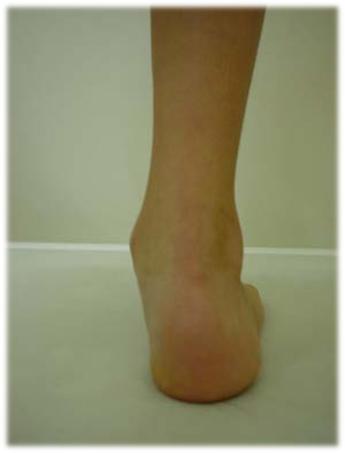

Pronación excesiva (pie plano)

Pie plano

El dolor de talón a veces resulta de una pronación excesiva. La pronación es el movimiento y aplanamiento normal del puente del pie que le permite adaptarse a las variaciones del suelo y absorber impacto al caminar normalmente.

La pronación excesiva puede también contribuir a dañar la cadera, la rodilla, y la parte baja de la espalda.

Pronación excesiva

Síntomas

• Ausencia del arco longitudinal que se observa cuando la persona está de pie.

• Dolor en el pie.

• El talón se inclina lejos de la línea media del cuerpo más de lo usual.

Tratamiento

Plantillas y realización de ejercicios sencillos (Puntillas, Talones, recoger cosas con los dedos de los pies). Caminar por terrenos naturales como arena o césped.

Una última consideración sobre el uso de plantillas, es que su finalidad no es la de restablecer una forma normal del pie, si no la de evitar el dolor. En todos los casos se aconseja el uso de calzado cómodo y evitar la obesidad.